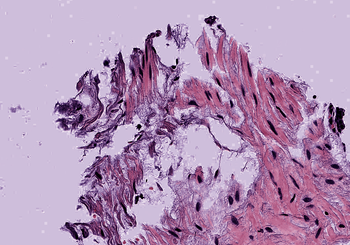

4.1 Quality of Color Normalization

A qualitative and quantitative comparison of the SPCN algorithm with other color normalization techniques is described in Vahadane et al. (2016), and justifies its choice as a starting point in this work. In Figure 2, we compare the performance of the original SPCN to our improved version on three challenging examples of source images taken from TCGA. On Image (a), the original SPCN exhibits swapping of stain color basis due to the presence of significant blue components in both stains. Our proposed improvement to compare the difference of red and blue components avoids this error. Image (b) illustrates that in cases where one stain dominates, SPCN can lead to a color tint in the intermediate whitespace. Our algorithm avoids this by estimating a channel-wise maximum pixel intensity. Image (c) shows an image with a significant background portion, which leads to a strong tinge in the background after normalization in an extreme case, which is also handled well in our results by estimating the maximum intensity for each channel separately.